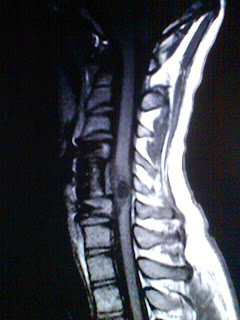

CERVICAL MRI W/WO

This patient's history really got to me and it is a very interesting exam to see. The images I posted do not look like the original because I took these with my camera phone off of the computer screen so the T1 and T2 weighted images are not windowed properly but it was the best I could get. You can still clearly see the pathology I am talking about. This young man is only 22 years old, the same age as my brother, so that is why I think I put so much emotion into this study. The parents of this patient were practically having to do everything for him. He had a motorized wheelchair with a joy stick because he had very little use of his upper extremities and had been paralized from the waist down. I assumed he was born like this until I screened him and got his history. Last summer he (being over six feet tall himself) dove head first into an above ground swimming pool and suffered severe trauma to his cervical spine. He had to have surgery fusing C4 to C6 with a large strut graft and fusion plate. His injury paralized him. I felt so much sorrow for him and his family because he was an average everyday young man and because of his injury he will have to endure many hardships from here on out. You could tell that he wasn't happy having to rely on his mother to physically care for him so much and that she was new to all this was apparent too. They let him do what he could on his own and he tried so hard to manuver onto the table using his arms, but that was the reason he had come for the MRI. The patient was having neck pain and bilateral upper extremity weakness. Once we started the scan we could tell the source of the symptoms. The patient has a 15mm cystic appearing intramedullary and intradural mass in the spinal cord at the level of C5 with surrounding edema. The radiologist stated in the report that this could be a neoplastic process or a post traumatic change and suggest a neurosurgical consult. The young age of the patient and the tragic history really made me stop and be thankful for my health and well being. I take so much for granted and patients and stories like these help me get back in focus. This was also a great study to learn from, I had never seen a pathology like this in the spinal cord. It is very interesting. I just wish we knew what happened to some patients post MRI or what the results of the pathology composition were.